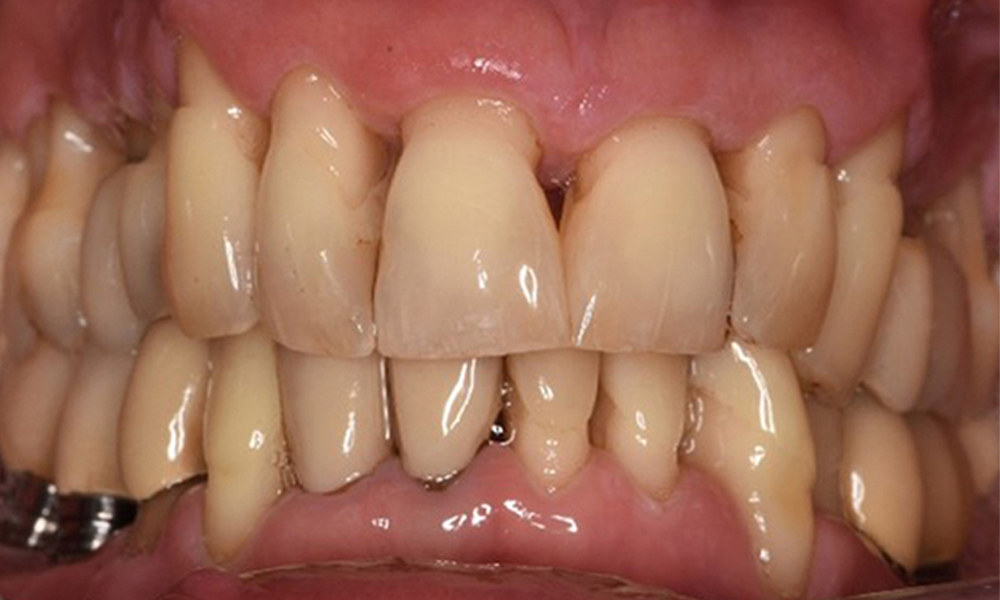

Oral hygiene and patient compliance are very good (see picture “front view”). All that is required is repeat instruction and motivation to maintain oral hygiene behaviour.

Front view of dentition (upper and lower jaw)

Front view